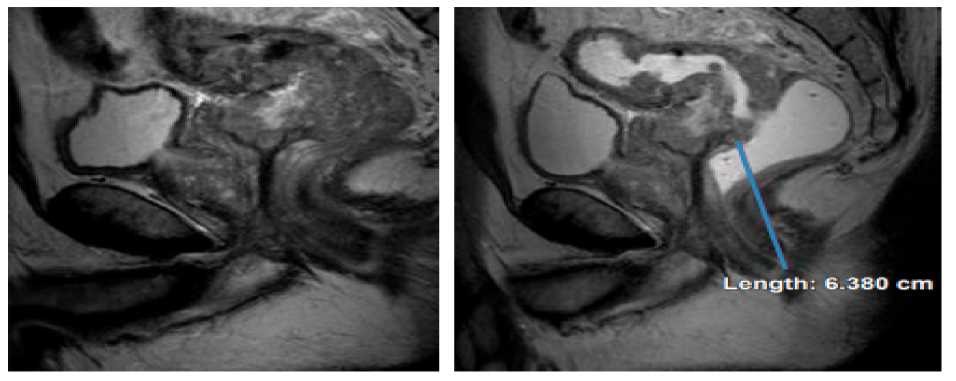

Romero, Domínguez, Sánchez, Carmona y Pérez (2022), en su estudio “Utilidad de la resonancia magnética en la estadificación del cáncer de recto”, presentan el caso de un paciente masculino de 64 años de edad, con cambios en los hábitos intestinales y sin antecedentes importantes que acude para valoración de recto mediante resonancia magnética, donde se detecta tumor en recto medio T4aN1b. Dicho estudio concluye que la resonancia magnética rectal es una pieza clave en la estadificación local de los pacientes con cáncer de recto antes y después del tratamiento, proporciona información anatómica detallada que permite identificar factores de riesgo para el manejo, adaptar el tratamiento y mejorar el pronóstico.(20)

Resonancia magnética: es un examen imagenológico en el que se usan imanes y ondas de radio potentes para poder observar diferentes imágenes del cuerpo, dependiendo de la zona que necesita de imágenes para confirmar o desechar un diagnóstico o sospecha de padecimiento de una enfermedad. La resonancia magnética rectal es la modalidad de imagen preferida para la estadificación local del cáncer de recto, ya que ayuda al radiólogo a describir la ubicación y la morfología del tumor, proporcionar sus categorías T y N, detectar la presencia de invasión vascular extramural, e identificar su relación con las estructuras circundantes, incluido el complejo de esfínteres y afectación de la fascia mesorrectal, además de la reestadificación después de la quimiorradioterapia neoadyuvante, es decir, la respuesta al tratamiento.(20)